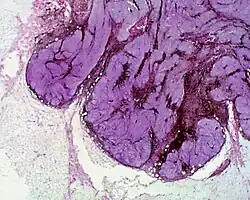

Micrograph of a blue nevus showing the characteristic pigmented melanocytes between bundles of collagen. H&E stain.

Cellular blue nevus